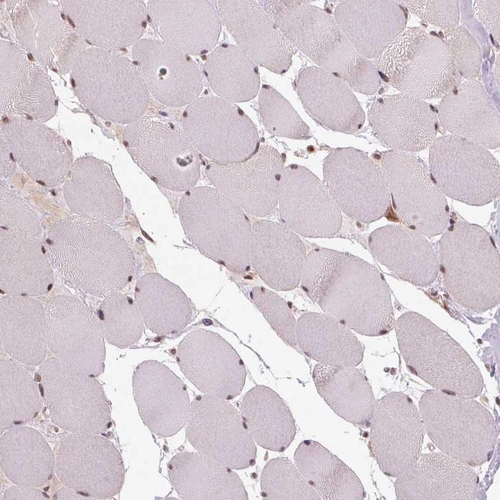

Immunohistochemical staining of human spleen shows moderate cytoplasmic positivity in cells in red pulp.